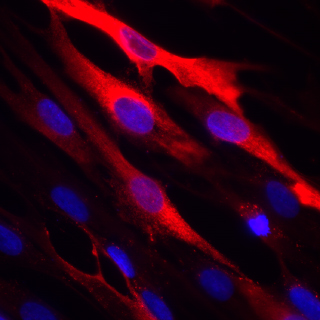

Cornell researchers have uncovered details of how the deadly Middle East respiratory syndrome coronavirus (MERS-CoV) enters host cells, findings that help explain how it can infect many cell types – a hallmark of viral pathogenicity. The results also offer possible new avenues for treatment.

The researchers discovered that a common protease enzyme known as furin activates the MERS-CoV to fuse with cell membranes and enter host cells.

Coronaviruses have a spike protein that is activated by a protease and mediates membrane fusion and entry into a host cell. The location on the spike protein where a protease activates this process is called a cleavage site.

The researchers found there were two cleavage sites for MERS-CoV, each activated by furin at different times: after a new virus is assembled inside a host cell, when the virus makes its way out of the host cell to the cell surface, and again, when the released virus finds a new cell and is taken up into the membrane.